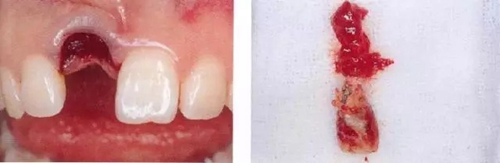

▲圖44-1,2

圖44-3

圖44-1~3 22歲,女性。交通事故3個(gè)月后來院。由于事故導(dǎo)致上頜右側(cè)前牙區(qū)凹陷且存在牙根吸收現(xiàn)象。圖片為初診時(shí)的前方照與根尖片。

▲圖44-4,5

圖44-6

圖44-4~6 拔牙后通過骨移植材以及結(jié)締組織移植(CTG)進(jìn)行GBR。